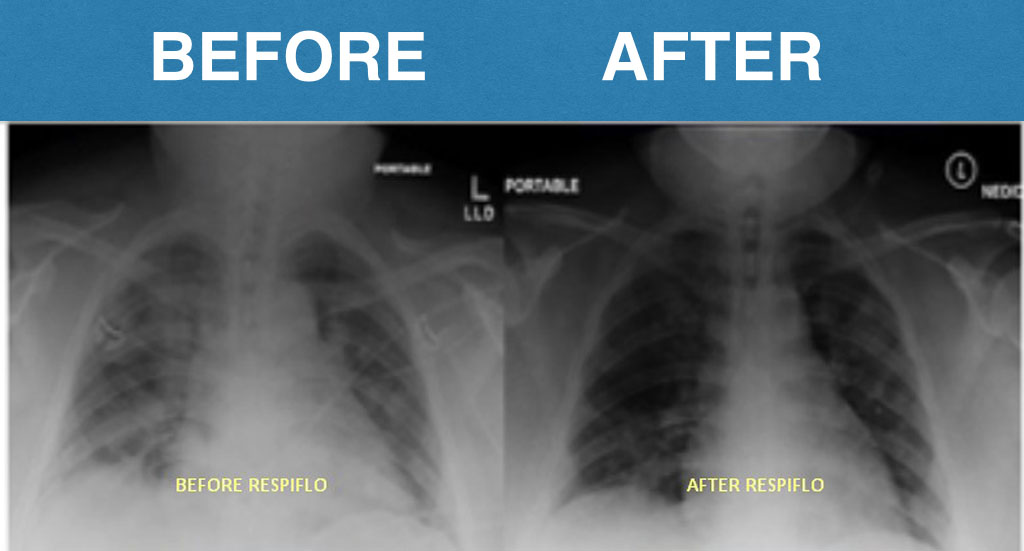

A few months ago my COPD symptoms were really limiting my daily life. Climbing stairs or carrying groceries would leave me struggling to catch my breath. My doctor ordered a chest X-ray, and when he showed it to me, the areas of congestion and reduced airflow were pretty obvious. Fortunately, tha'ts when I started following the routine and stuck with it every day. I chose the full 6 month treatment, but just after 7 weeks, I noticed my chest didn’t feel as heavy and I could take fuller breaths. At my next checkup, another X-ray was taken. My doctor said my lungs appeared less congested than before and my breathing capacity seemed improved during testing.

A few months ago my COPD had gotten so bad I could barely climb the stairs without stopping. My doctor showed me my lung X-ray and said my lungs looked pretty congested. It honestly scared me. I ordered the 4 bottle discounted offer and started doing the breathing method from the video every day. A few weeks later I went back for another checkup and when my doctor was shocked when he saw the new X-ray. My lungs looked much clearer, and I could really feel the difference in how much easier it is to breathe now.